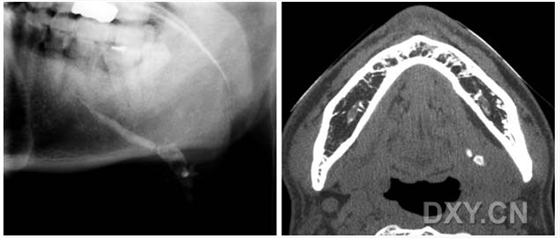

涎石病